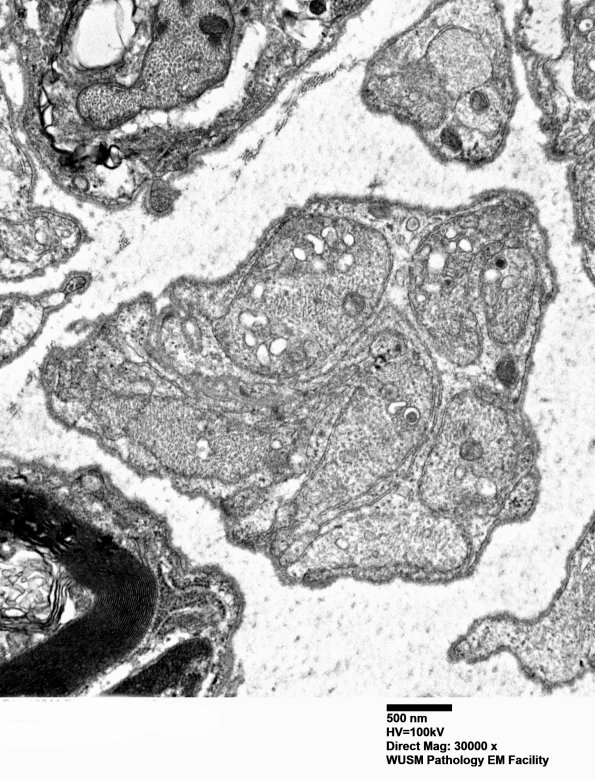

Washington University Experience | PERIPHERAL NEUROPATHY | 1 NORMAL NERVE ANATOMY | 6 Infant Peripheral Nerve | 1B9 (Case 1) Blk2 EM 030 - Copy

These axons are discernible and, by size, are likely to represent axons destined to become unmyelinated fibers. (electron micrograph)